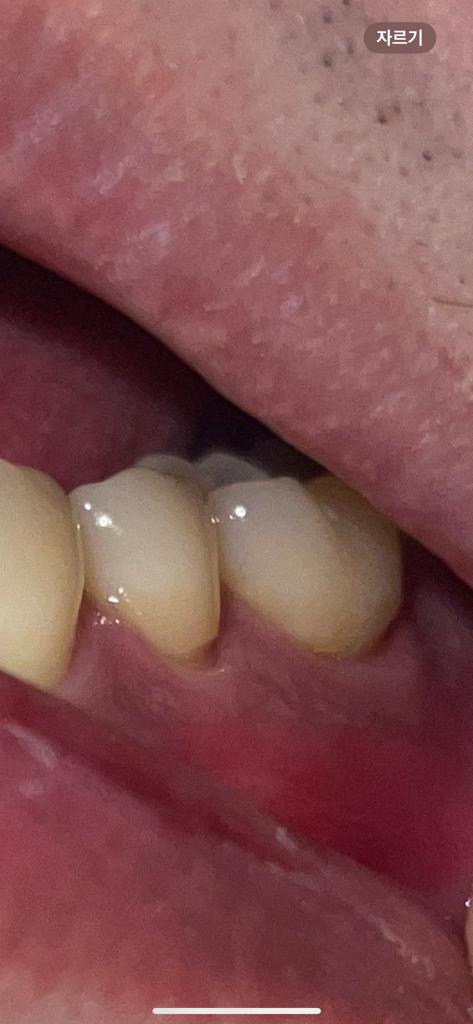

잇몸이 약간 내려가기는 했으나 심각한 정도는 아닙니다. 앞으로 관리를 잘해주시면 되겠습니다.

치경부 마모증이 시작되는거 같습니다. 시린증상이 잇다면 치료를 받으시고 괜찮으시면 양치를 너무 강하게 하지 않는게 중요합니다 .

치아의 옆 부분에 마모층이 생기게 되면 시립 증상이 있을 수 있습니다. 이런 시린 증상은 대부분 시간이 지나서 줄어들지만 증상이 지속된다면 해당 부위를 치과재료로 충전해 줄 수 있습니다. 마모가 진행되지 않도록 양치질을 할 때 너무 과도한 힘으로 치아를 솔질을 하지 않는 것이 좋습니다.

현재 치경부에 마모가 있는 것은로 보이며, 해당부위를 방치하는 경우 치아시림이 발생할수 있기에 레진으로 메꾸는 치료를 받길 권합니다.

잇몸퇴축이 다소 있긴 한데 심한편은 아닙니다 잇몸관리 꾸준히 잘해주시고 시린이 치약을 사용해보셔도 좋을 것 같습니다